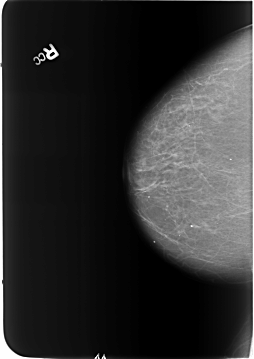

Volume: benign_without_callback_01 Case: B-3179-1

B_3179_1.RIGHT_CC

RIGHT_CC LINES 5736 PIXELS_PER_LINE 4064 BITS_PER_PIXEL 12 RESOLUTION 50 NON_OVERLAY